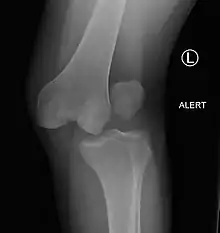

| Plain lateral X-ray of the left knee showing a posterior knee dislocation[1] | |

Plain X-rays, CT scan, ultrasonography, or MRI may help with the diagnosis.[2][11] Findings on X-ray that may be useful among those who have already reduced include a variable joint space, subluxation of the joint, or a Segond fracture.[5]